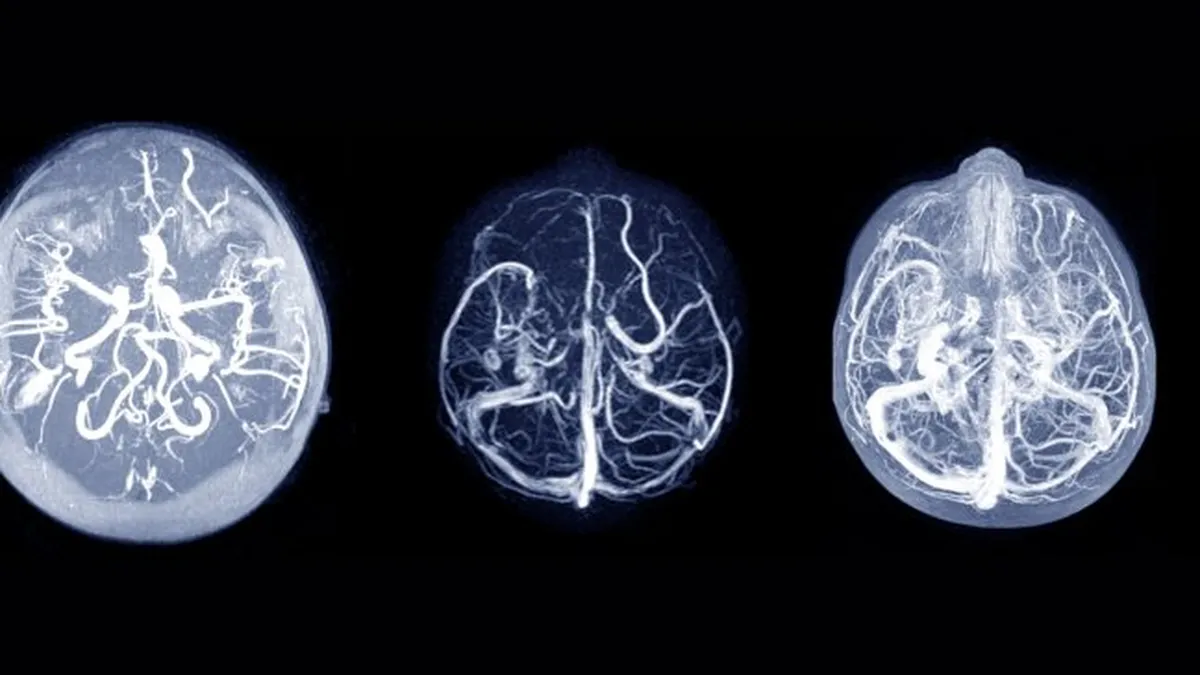

La causa de la convulsión sufrida por Javier Altamirano fue una trombosis del seno longitudinal superior. (Foto: archivo)

Los senos cerebrales son estructuras venosas ubicadas en la superficie del cerebro, encargadas de drenar la sangre venosa del mismo y funcionan como conductos principales por donde fluye este tipo de sangre.

Entre los senos venosos del cráneo, el seno sagital o longitudinal superior, que discurre a lo largo de la línea media entre los hemisferios cerebrales, es uno de los más significativos. Según el parte médico de Estudiantes, es en este seno donde se produjo la trombosis que desencadenó la convulsión de Altamirano.